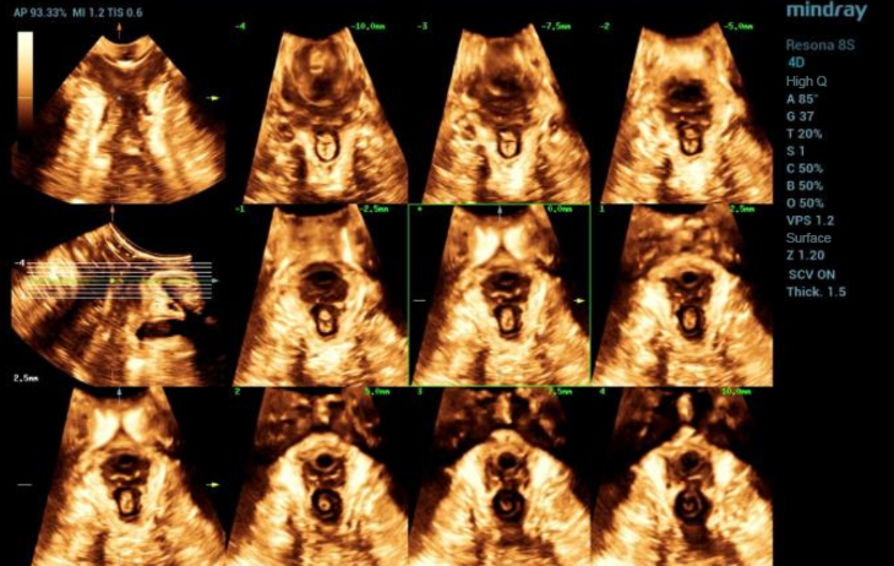

?? ?? ????? parasagittal view??? ???/?? 2D ???, 3D/4D ?? ??, Ipage+?? ?? ?? ?? ???? ?????.

?? 39??? 30???(G1P1)?? ??? Negative-pressure vacuum extraction? left perineotomy? ?????, ???? ???? 3.387kg?????. Pelvic floor ???? ?? 42? ? ???????.

- Ipage+ : ? ? ??? slice?? ?? ?? ?? levator avulsion? ?? ??, levator trauma ??? ??? ? ? ??.